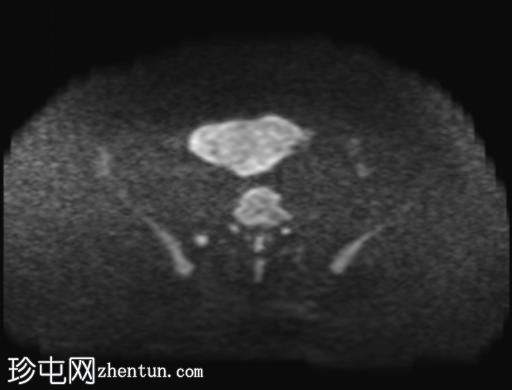

盆腔内可见多个边界清晰的肿块:

其中一个位于子宫上方,T2加权像呈中等信号,中心区域呈高信号,增强T1脂肪抑制像未见强化。右侧卵巢增大,增厚的血管蒂扭曲,未见强化,轴位和矢状位T2加权像均显示清晰。

另一个位于子宫后窝,T2加权像呈中等信号,增强扫描显示明显强化。

2个月前进行的MRI检查显示双侧卵巢肿块均有强化,右侧卵巢肿块未见扭转。

Krukenberg瘤患者单侧卵巢扭转的MRI特征。

Krukenberg瘤引起的卵巢扭转在文献中鲜有报道。